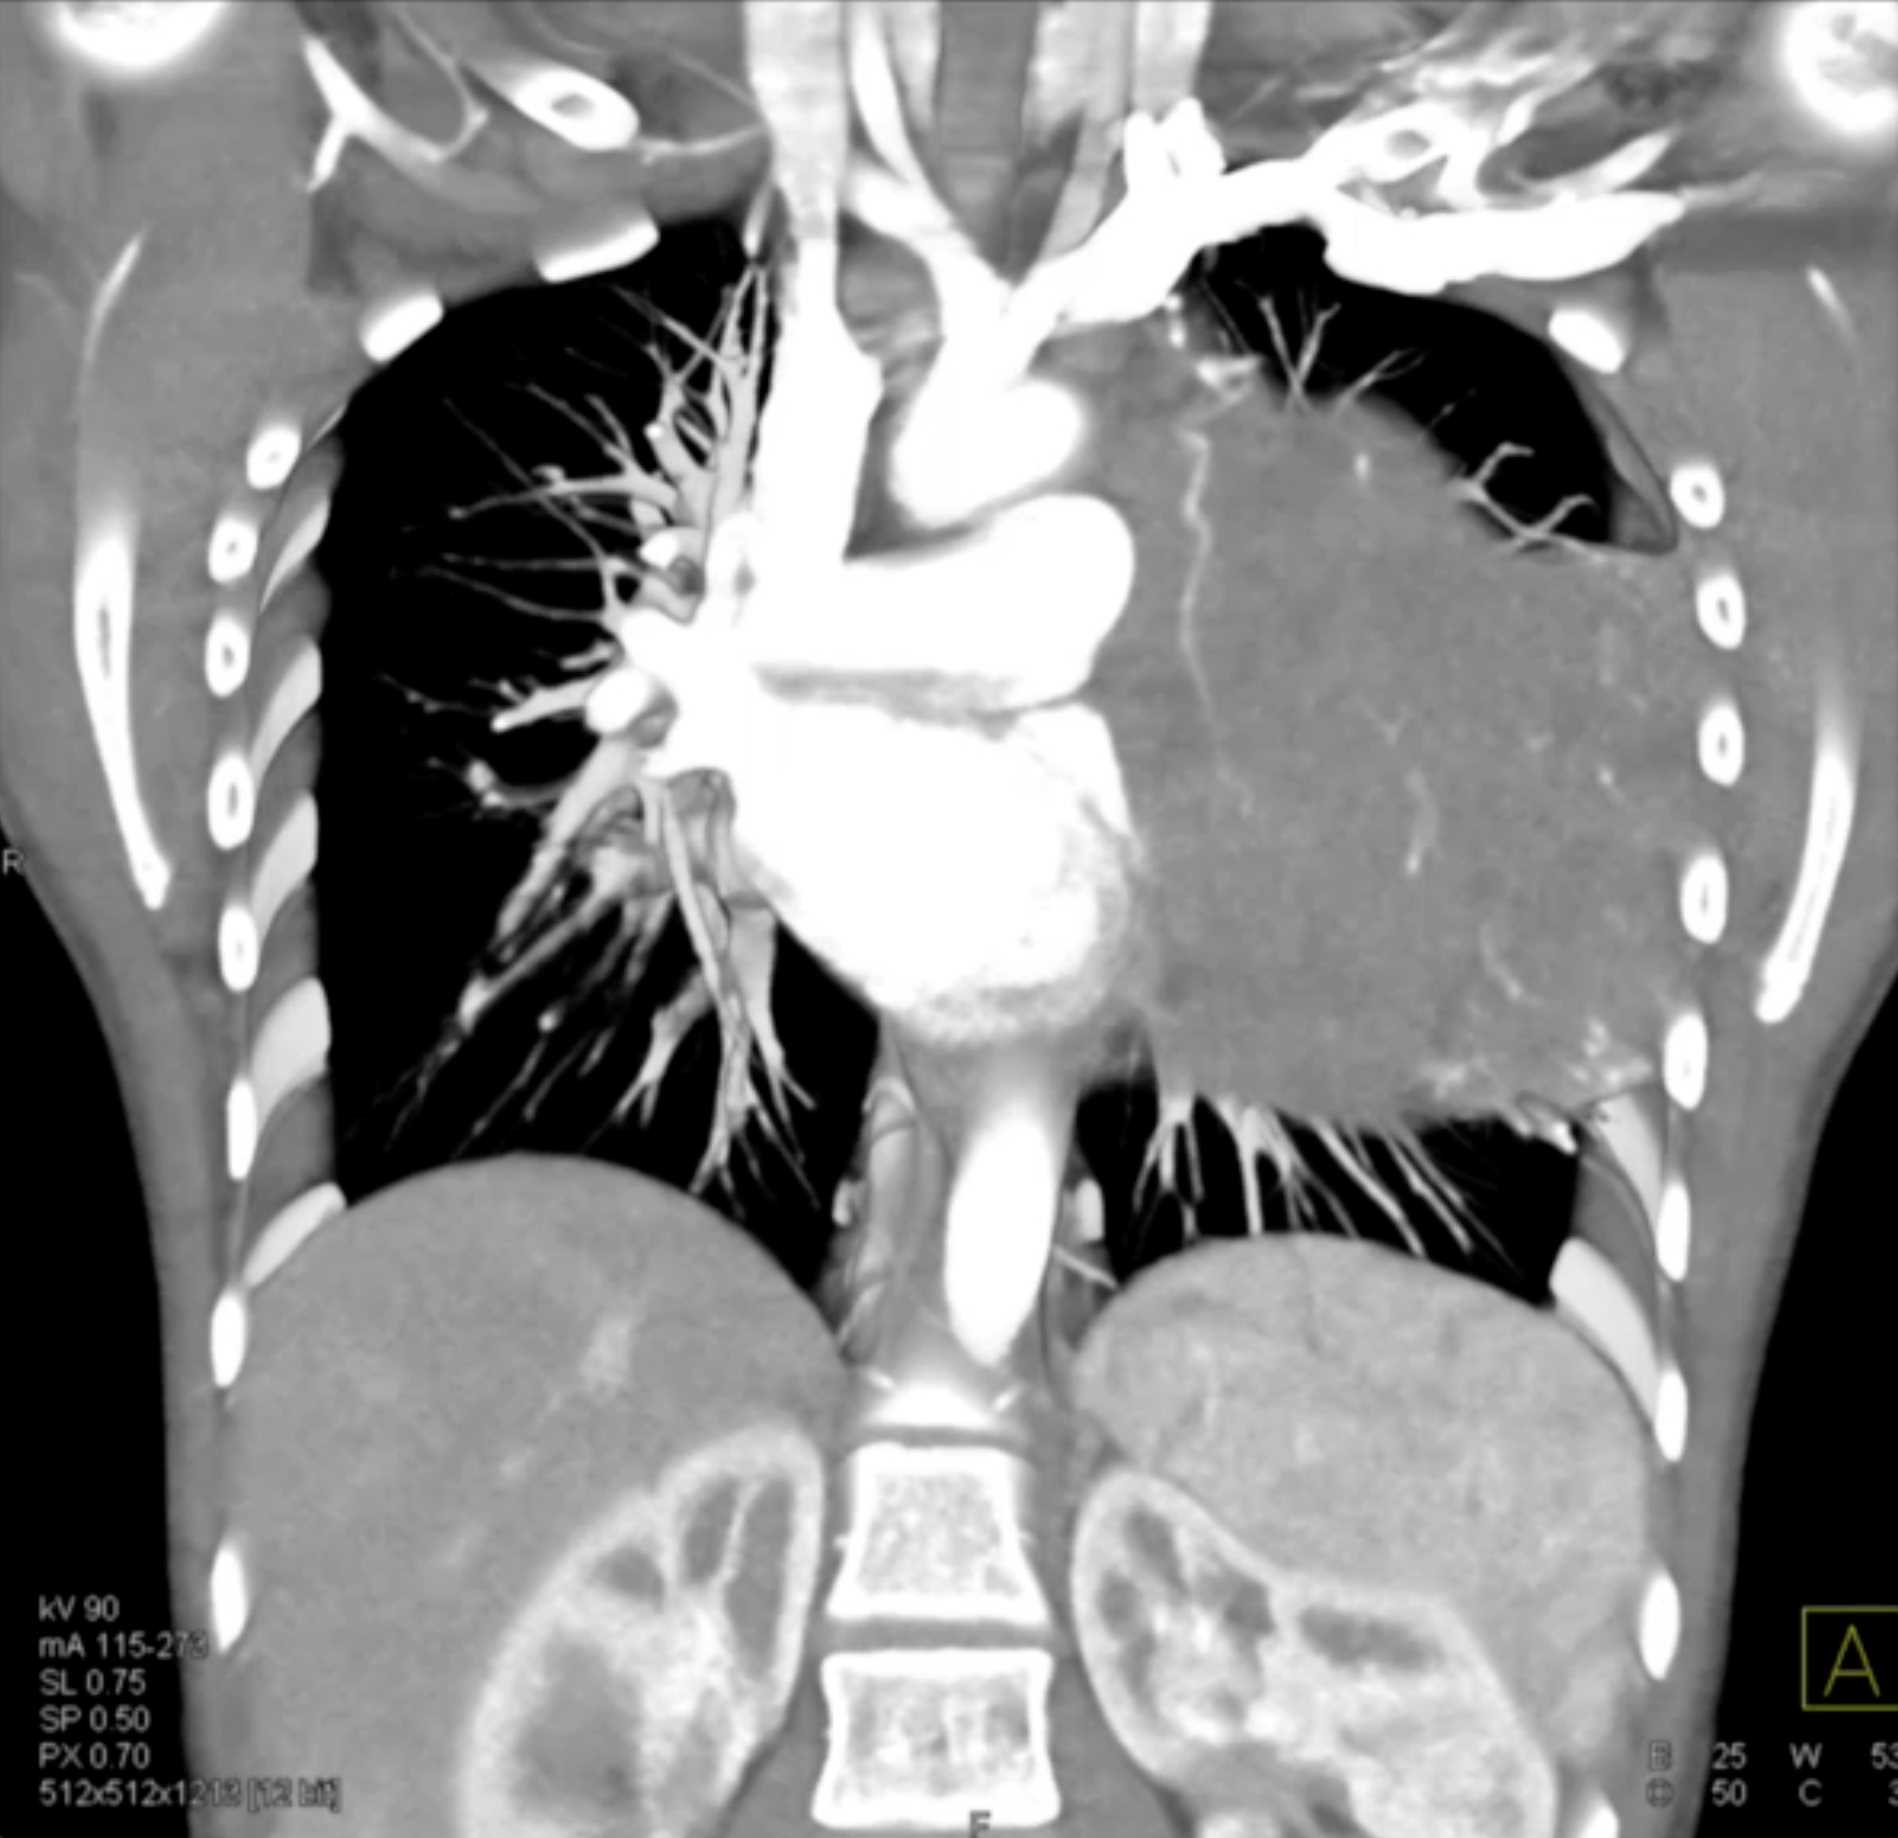

Subtle Adenocarcinoma Pancreas